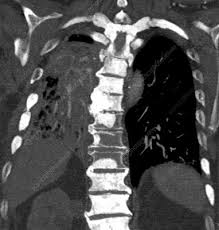

Can A Ct Scan Show Breast Cancer - Best Scans To Detect Cancer Envision Radiology : After detecting the location of the tumor, the area will be biopsied for testing in the lab.. Ct scans are inaccurate for treatment monitoring after cancer treatment, a ct scan is unable to determine whether masses leftover are cancerous: The area covered in the scanning can be determined. Bone scans, positron emission tomography (pet), and computed tomography (ct) all continue to be employed alone or in combination for the detection of breast cancers suspected to have spread. But the risk associated with these tests is worth the benefit, in most cases. A sentinel lymph node biopsy may first be performed to determine whether cancer has spread to the lymph glands under the arm.

The contrast helps to show up areas of increased vascularity and so it does help show up tumours as they have a rich blood supply. Ct scans are inaccurate for treatment monitoring after cancer treatment, a ct scan is unable to determine whether masses leftover are cancerous: Doctors often use this is for cancer staging. When a breast cancer has been diagnosed, some people have a ct scan of their chest and tummy (abdomen) to stage the breast cancer. The specialized cone beam breast ct (cbbct) scanner, developed by boone and colleagues, uses the same amount of radiation as a conventional mammogram.

Knowing the stage helps your doctor decide which treatment you need. So far, researchers at the university have. Doctors often use this is for cancer staging. Mammography is currently the preferred examination for breast cancer screening; During a ct scan, you will be exposed to a small amount of radiation. The area covered in the scanning can be determined. The test has only a limited ability to detect small tumors. The cancer's stage describes the location of cancer, if it spread and if it's changing the function of your organs. A breast pet scan is often very specific and sensitive and is approved for patients. One example is a combined pet and ct scan (known as pet/ct), available in some centers. The specialized cone beam breast ct (cbbct) scanner, developed by boone and colleagues, uses the same amount of radiation as a conventional mammogram. Ct scans can show a tumor's shape, size, and location. The contrast helps to show up areas of increased vascularity and so it does help show up tumours as they have a rich blood supply.

18 F Fdg Uptake Of Bone Marrow On Pet Ct For Predicting Distant Recurrence In Breast Cancer Patients After Surgical Resection Ejnmmi Research Full Text from media.springernature.com Can a ct scan pick up breast cancer. Pet scans are not used to screen women for breast cancer. The test has only a limited ability to detect small tumors. The cancer's stage describes the location of cancer, if it spread and if it's changing the function of your organs. Doctors often use this is for cancer staging. Ct scans can show a tumor's shape, size, and location. When a breast cancer has been diagnosed, some people have a ct scan of their chest and tummy (abdomen) to stage the breast cancer. Bone scans, positron emission tomography (pet), and computed tomography (ct) all continue to be employed alone or in combination for the detection of breast cancers suspected to have spread.

Doctors often use ct scans to help them guide a needle to remove a small piece of tissue. Some fear that the ionizing radiation emitted from ct scans can harm dna and cause tumors. A sentinel lymph node biopsy may first be performed to determine whether cancer has spread to the lymph glands under the arm. When a breast cancer has been diagnosed, some people have a ct scan of their chest and tummy (abdomen) to stage the breast cancer. This helps determine whether or not the cancer can be removed with mastectomy. Ct scans are inaccurate for treatment monitoring after cancer treatment, a ct scan is unable to determine whether masses leftover are cancerous: This can allow for examination of neighboring organs and structures like lymph nodes to check for any signs of disease. This is an excellent way to take a needle biopsy for inflammatory breast cancer because imaging can show the best place to take the biopsy. In some cases, physicians use all three imaging techniques. Bone scans, positron emission tomography (pet), and computed tomography (ct) all continue to be employed alone or in combination for the detection of breast cancers suspected to have spread. It's an effective imaging test for finding cancer and learning its stage. How do ct scans work? The contrast helps to show up areas of increased vascularity and so it does help show up tumours as they have a rich blood supply.

Breast Mri Fact Sheet Westmead Bci from www.bci.org.au The ct scan might show signs of cancer, but that cancer might not be active for example, it could be scar tissue left over from cancer killed off by your treatment Once doctors know where to look, further evaluation can be done with other techniques. This test is most often used to look at the chest and/or belly (abdomen) to see if breast cancer has spread to other organs. The cancer's stage describes the location of cancer, if it spread and if it's changing the function of your organs. Breast pet scans are known as positron emission mammography (pem). The benefits of having a ct scan usually outweigh the risks. During a ct scan, you will be exposed to a small amount of radiation. When a breast cancer has been diagnosed, some people have a ct scan of their chest and tummy (abdomen) to stage the breast cancer.